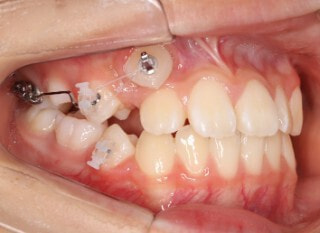

前歯装置装着時

小児期第一段階

終了時